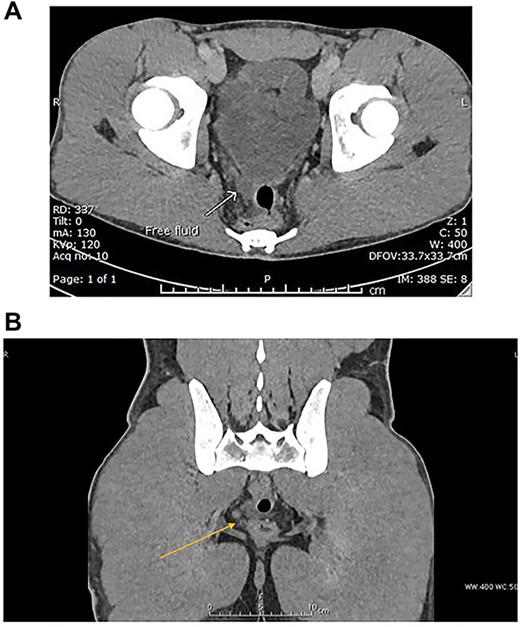

CT scan of abdomen and pelvis with IV contrast was performed (Fig. 4A and B).

(A) Venous phase axial CT scan showing minimal amount of free fluid in the Douglas pouch (retro-vesical). (B) Venous phase coronal CT scan showing minimal amount of free fluid in the Douglas pouch (retro-vesical).

Mild free fluid in the pelvis.

No intra-abdominal solid organ injury.

No free air.

No bony injuries.